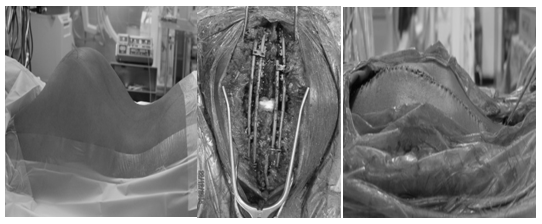

Halo gravity traction was maintained over a 4 month period with resultant improvement in curve magnitude from 135° to 119° and a lumbar lordosis from 111° to 94°. Surgical treatment consisted of posterior fusion, vertebral column resection of the 9th and 10th thoracic vertebrae, with posterior segmental spinal instrumentation from the 3rd thoracic vertebra to the 3rd Lumbar vertebra and an interbody cage inserted at the site of the resection (Figure 8-10). The estimated blood loss for the entire procedure, which lasted for 360minutes, was 1,100mls. The surgery was performed with sensory and motor neuro-monitoring and there was no intraoperative neuro monitoring changes during the whole procedure. We maintained a mean arterial blood pressure of 70 to 80 mmHg and also gave pre op and intraoperative infusion of tranexamic acid.

Figure 8 Pre-Op. On-Table.

Figure 9 Intra-Op View.

Figure 10 Post-Op. On-Table Lateral View.